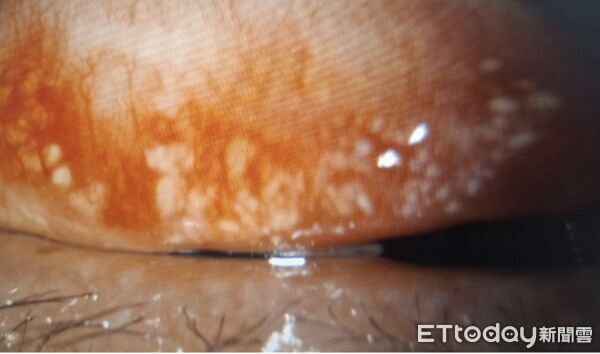

▲右上眼瞼內,有大群的眼結石彼此連結,推估約300顆。(圖/洪啟庭醫師提供)

進一步以裂隙燈檢查後,醫師發現患者上下眼瞼結膜內藏有大量眼結石,且分布相當密集,右眼上下眼瞼內各約數百顆,左眼上下眼瞼內也有大批眼結石,兩眼整體粗估接近千顆,由於部分結石已突出於結膜表面,患者每次眨眼時,都像有異物持續摩擦眼球表面,這也是造成疼痛、紅癢與角膜受損的重要原因。